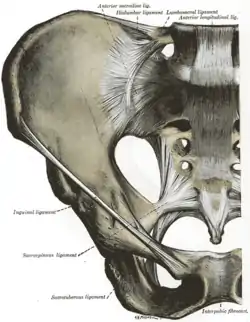

Ligaments

The ligaments of the sacroiliac joint include the following:[2]

- Anterior sacroiliac ligament

- Interosseous sacroiliac ligament

- Posterior sacroiliac ligament

- Sacrotuberous ligament

- Sacrospinous ligament

The anterior ligament is not much of a ligament at all and in most cases is just a slight thickening of the anterior joint capsule. The anterior ligament is thin and not as well defined as the posterior sacroiliac ligaments.

The posterior sacroiliac (SI) ligaments can be further divided into short (intrinsic) and long (extrinsic).[9] The dorsal interosseous ligaments are very strong ligaments. They are often stronger than bone, such that the pelvis may actually fracture before the ligament tears. The dorsal sacroiliac ligaments include both long and short ligaments. The long dorsal sacroiliac joint ligaments run in an oblique vertical direction while the short (interosseous) runs perpendicular from just behind the articular surfaces of the sacrum to the ilium and functions to keep the sacroiliac joint from distracting or opening. The sacrotuberous and sacrospinous ligaments (also known as the extrinsic sacroiliac joint ligaments) limit the amount the sacrum flexes.

The ligaments of the sacroiliac joint loosen during pregnancy due to the hormone relaxin; this loosening, along with that of the related symphysis pubis, permits the pelvic joints to widen during the birthing process. The long SI ligaments may be palpated in thin persons for pain and compared from one side of the body to the other; however, the reliability and the validity of comparing ligaments for pain have currently not been shown. The interosseous ligaments are very short and run perpendicular from the iliac surface to the sacrum, they keep the auricular surfaces from abducting or opening/distracting.